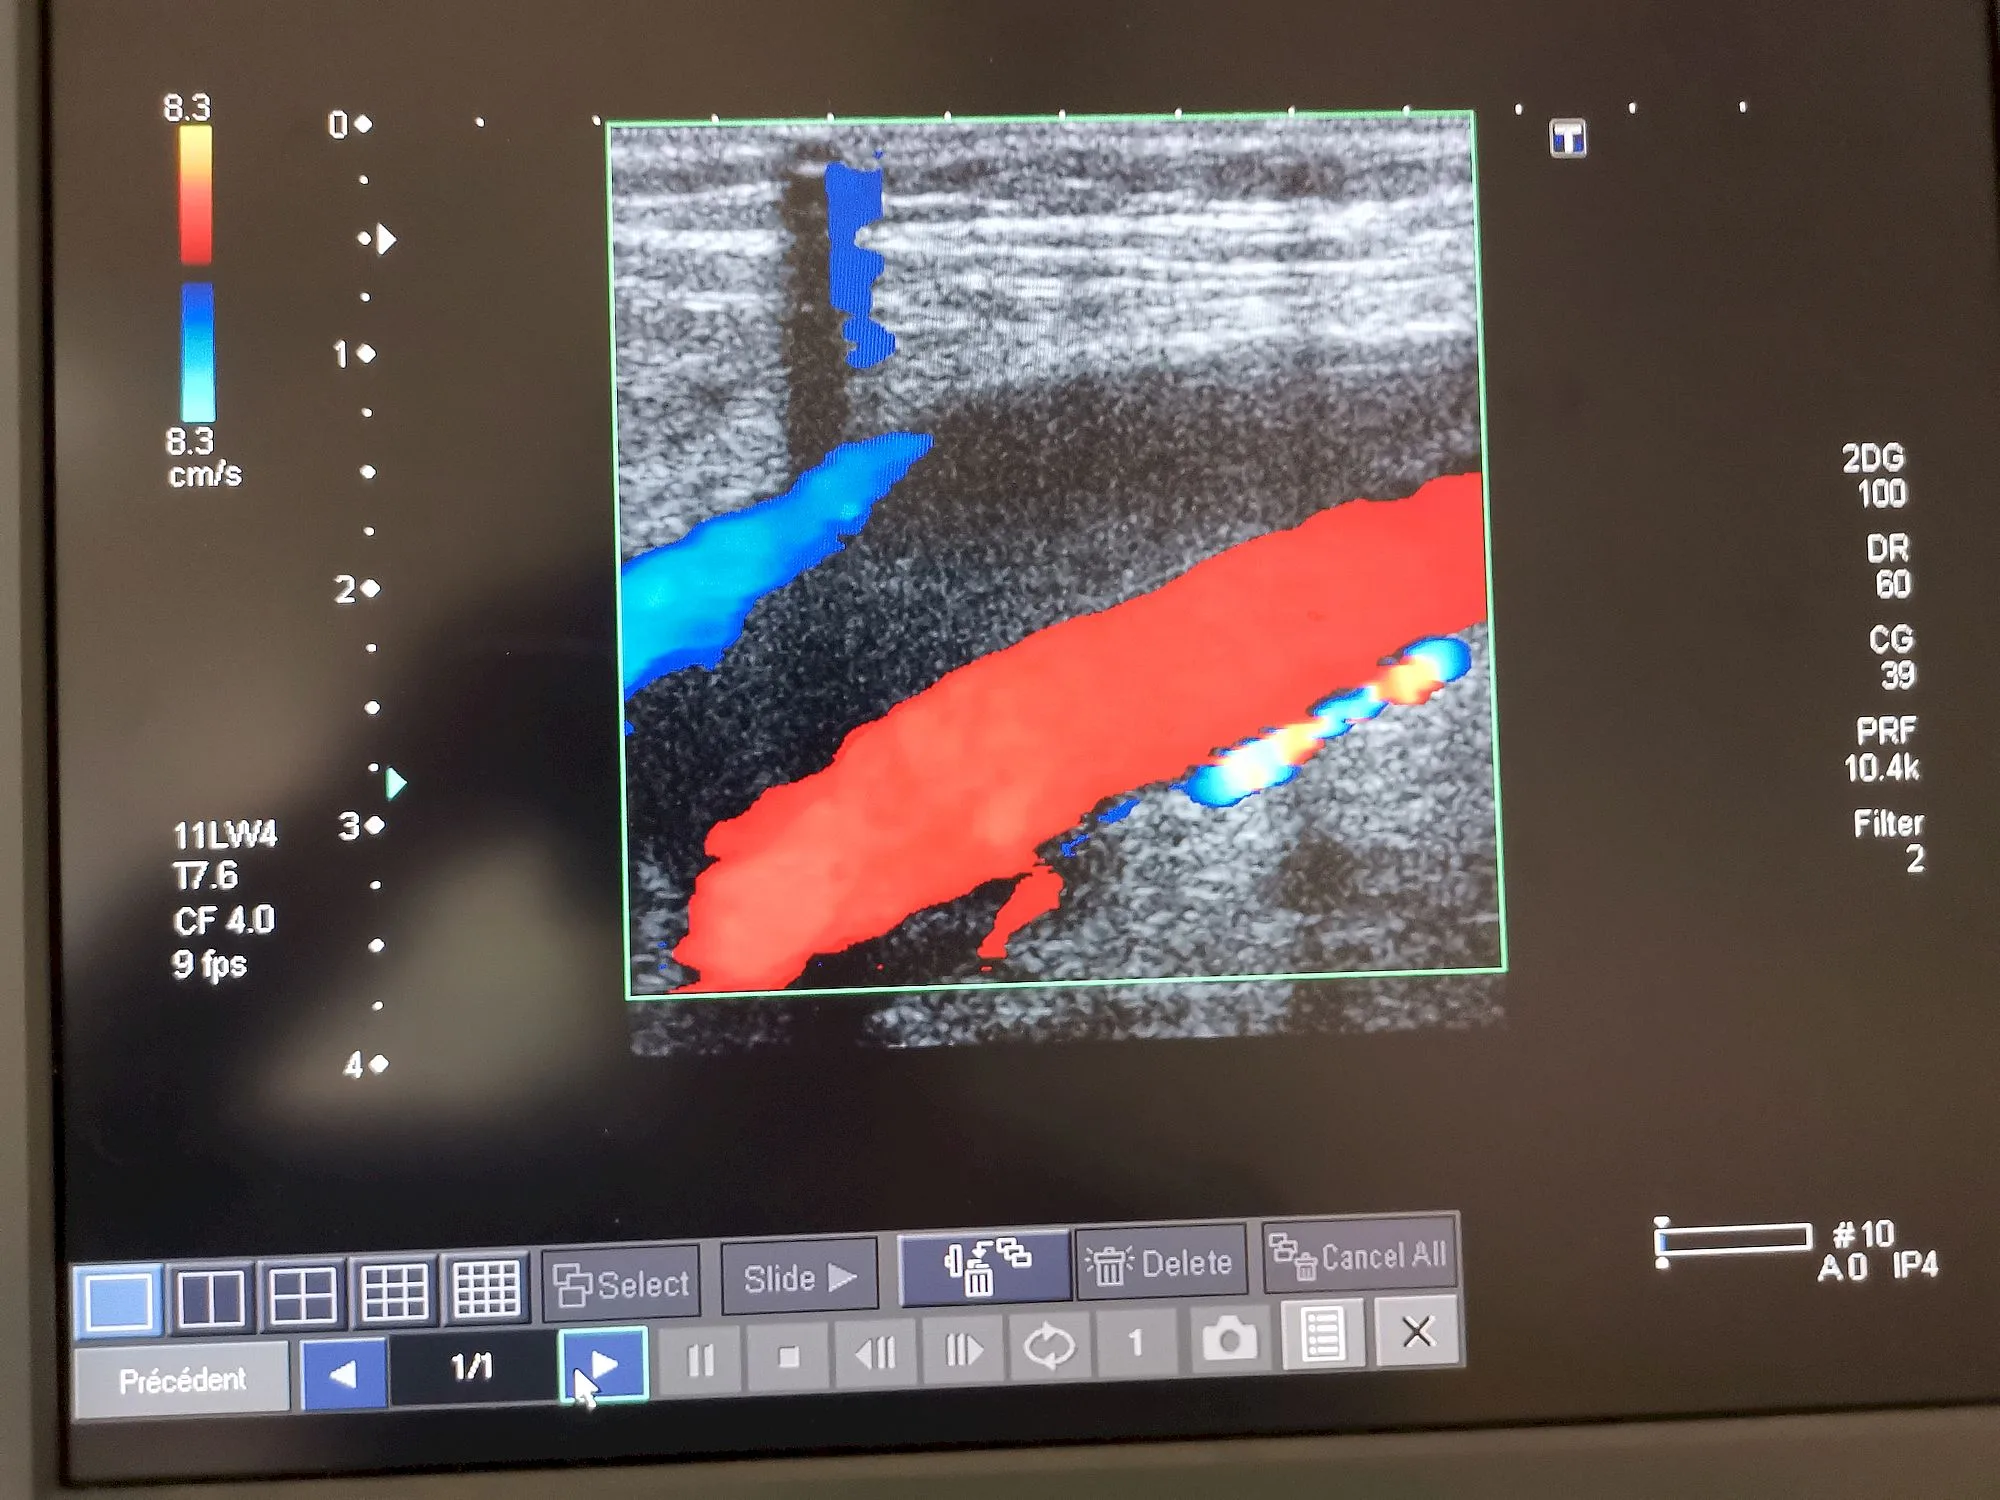

il faut traiter les patients le début , et la confrontation avec les problèmes de coagulation, des phlébites ,et même des embolies pulmonaires,

La découverte de l’équipe du Professeur Eric Delabrousse au CHU de Besançon va vraisemblablement permettre de sauver davantage de vies parmi les patients Covid-19 gravement touchés au plan respiratoire. Grâce à un angioscanner pulmonaire qui révèle les embolies pulmonaires non détectées jusqu’alors.